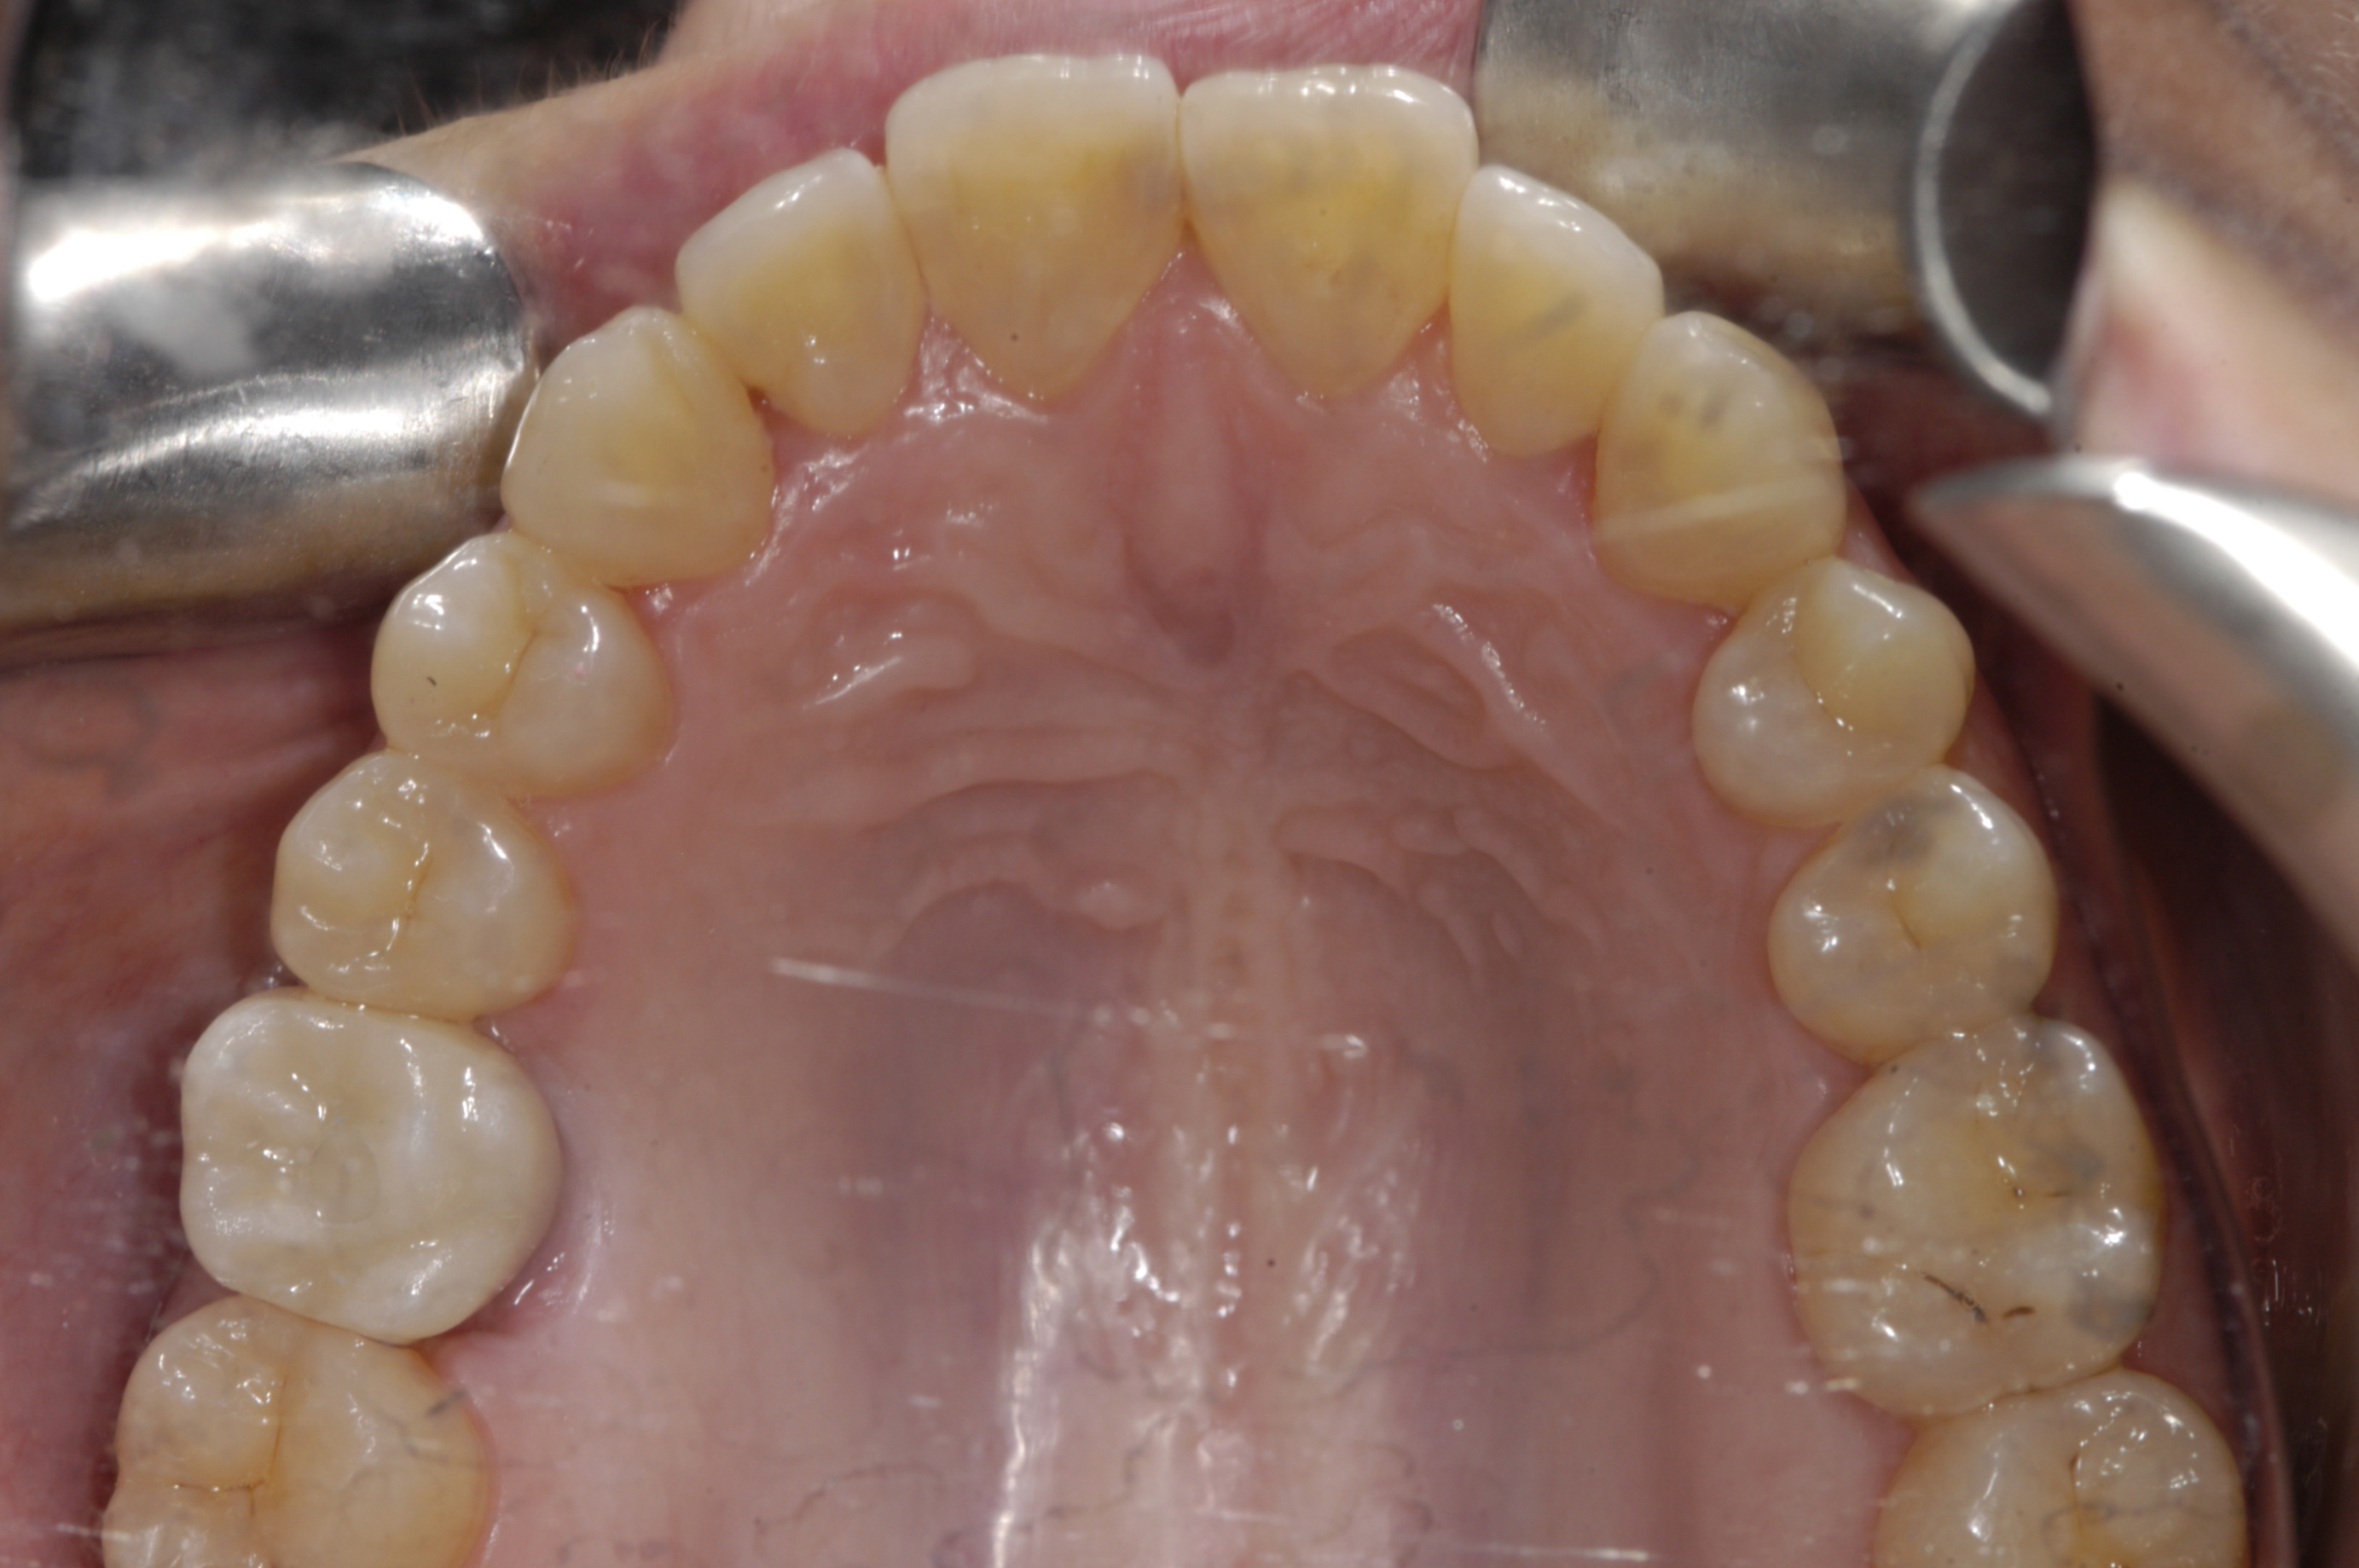

Finally, the amount of attached gingiva is evaluated. There is disagreement regarding the need for attached gingiva around implants,16,17 but the generally accepted minimum is 2 mm.18,19 A zone of 3 mm is recommended by this protocol for esthetics. A simple method of evaluation is to place a periodontal probe against the cementoenamel junctions of the adjacent teeth. At the midpoint between the adjacent teeth, the buccal aspect of the implant should exit 2 mm lingual to the probe. Therefore, if attached gingiva extends 1 mm facial to the probe, there should be adequate keratinized tissue. If the minimum requirements of bone volume and attached gingiva are not met, ridge augmentation and/or soft-tissue grafting are needed prior to implant placement. If the minimum requirements are met, digital impressions of both arches are obtained before dismissing the patient.